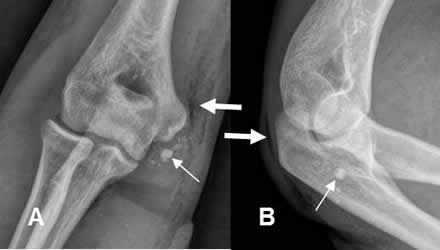

Fig 56. Cuerpo extraño.

A: Rx AP y B: Rx lateral. Trauma directo en el codo, con imágenes redondeadas y densas en la parte medial, que corresponden a cuerpos extraños. (Flechas delgadas). Igualmente se identifica aire en los tejidos blandos. (Flechas gruesas).